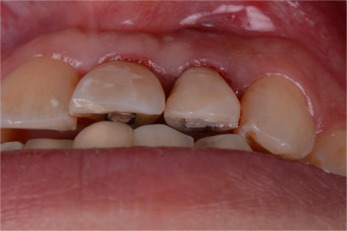

Fig. 11

Fig. 11.

Occlusion cleared of any static and dynamic contacts.